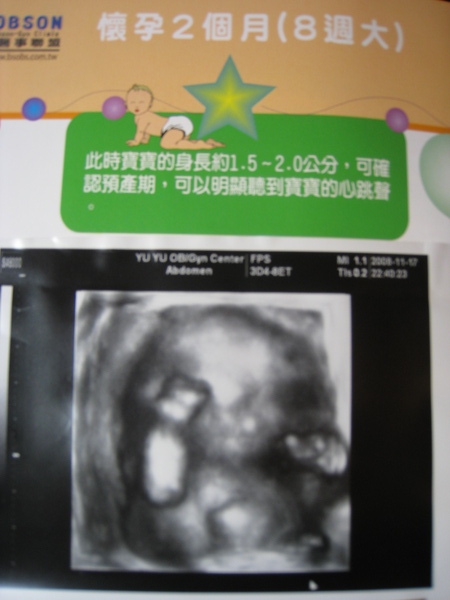

直到,昨天去看了3D超音波..

那小小圓圓的頭,小小圓圓的手手腳腳,還有小小圓圓的身軀...

尤其,3D彩色的小柚子,整個就像個小泥娃娃一樣曲在那..